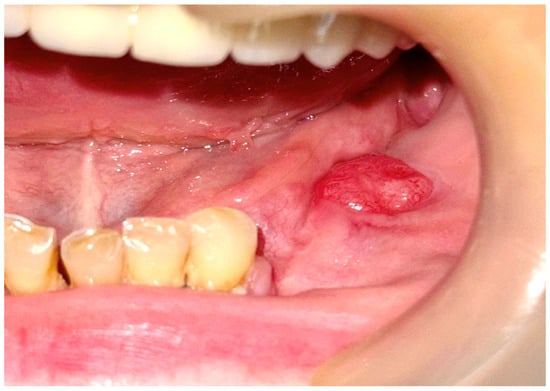

2.2. First Surgical Intervention